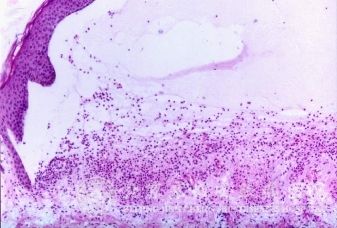

北京京城皮肤医院指出,尖锐湿疣的空泡化*:在尖锐湿疣的病理涂片中一种*的核周围有晕环,它占据了*浆的大部分,而将*浆压缩到边缘呈浓缩状,此种*称为空泡化*,它来源于浅层的鳞状上皮*。